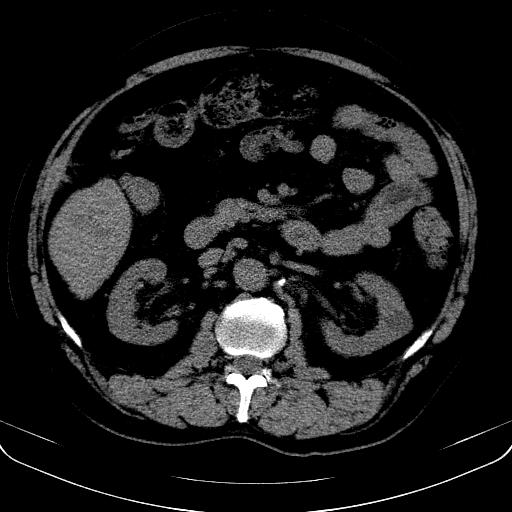

以下是引用jia119在2008-3-5 13:31:00的发言:[br]肝内多发片状低密度影,密度不均,我还是考虑肝ca可能,另肝内小囊肿,胆囊增大。

以下是引用形影不离在2008-3-5 12:18:00的发言:[br]肝硬化伴门脉高压征,肝内占位待排,增强再说.

以下是引用随光逐影在2008-3-5 21:11:00的发言:[br]肝硬化伴门脉高压(食管下段静脉曲张),肝癌不排除。建议:行ct增强扫描检查。

以下是引用同在2008-3-5 13:56:00的发言:[br]考虑肝癌可能性大,胆囊增大.